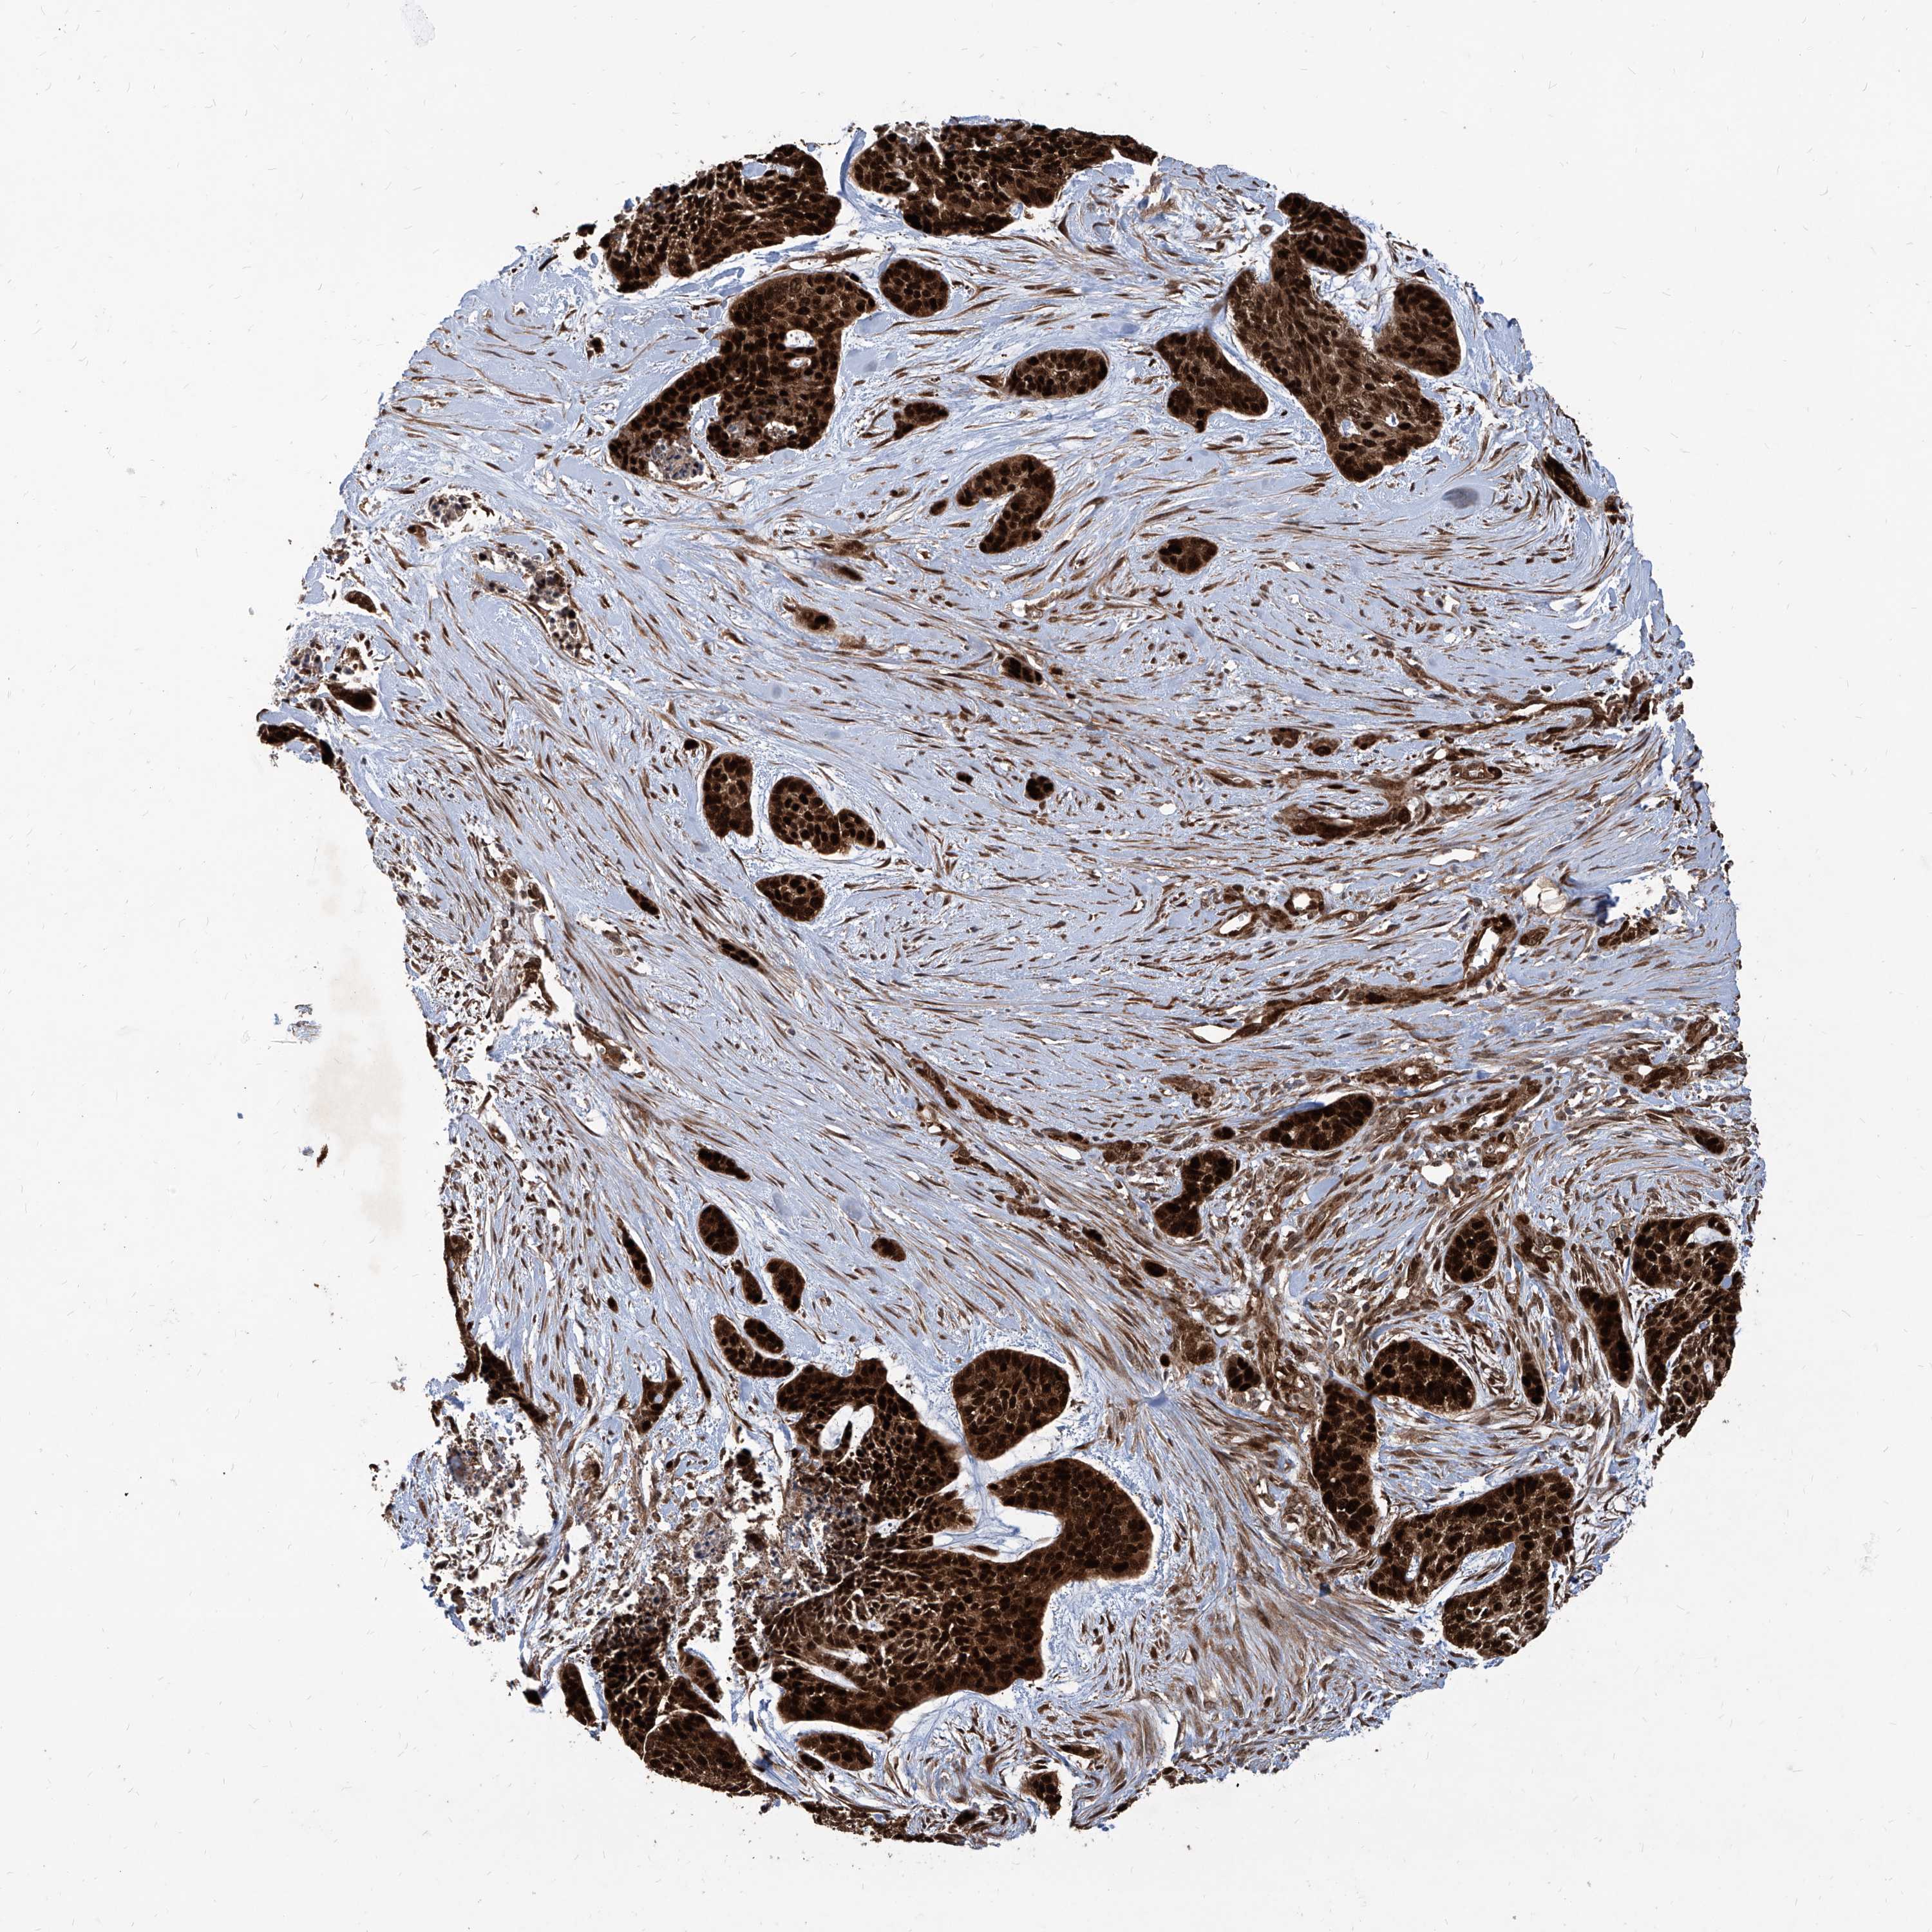

Basal cell and squamous cell cancer

SKIN CANCER - Protein expressioni

A mouse-over function shows sample information and annotation data. Click on an image to view it in a full screen mode. Samples can be filtered based on level of antibody staining by selecting one or several of the following categories: high, medium, low and not detected. The assay and annotation is described here.

Antibody stainingi

Antibody staining in the annotated cell types in the current human tissue is reported as not detected, low, medium, or high, based on conventional immunohistochemistry profiling in selected tissues. This score is based on the combination of the staining intensity and fraction of stained cells.

Each image is clickable and will lead to virtual microscopy that enables deeper exploration of all samples and also displays staining intensity scores, fraction scores and subcellular localization as well as patient and tissue information for each sample.

Antibody HPA031572

Staining

High

Medium

Low

Not detected

Intensity

Strong

Moderate

Weak

Negative

Quantity

>75%

75%-25%

<25%

None

Location

Nuclear

Cytoplasmic/membranous

Cytoplasmic/membranous,nuclear

Squamous cell carcinoma, NOS

Squamous cell carcinoma, metastatic, NOS